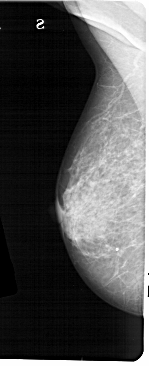

A_1473_1.LEFT_CC

LEFT_CC LINES 5341 PIXELS_PER_LINE 2326 BITS_PER_PIXEL 12 RESOLUTION 43.5 NON_OVERLAY